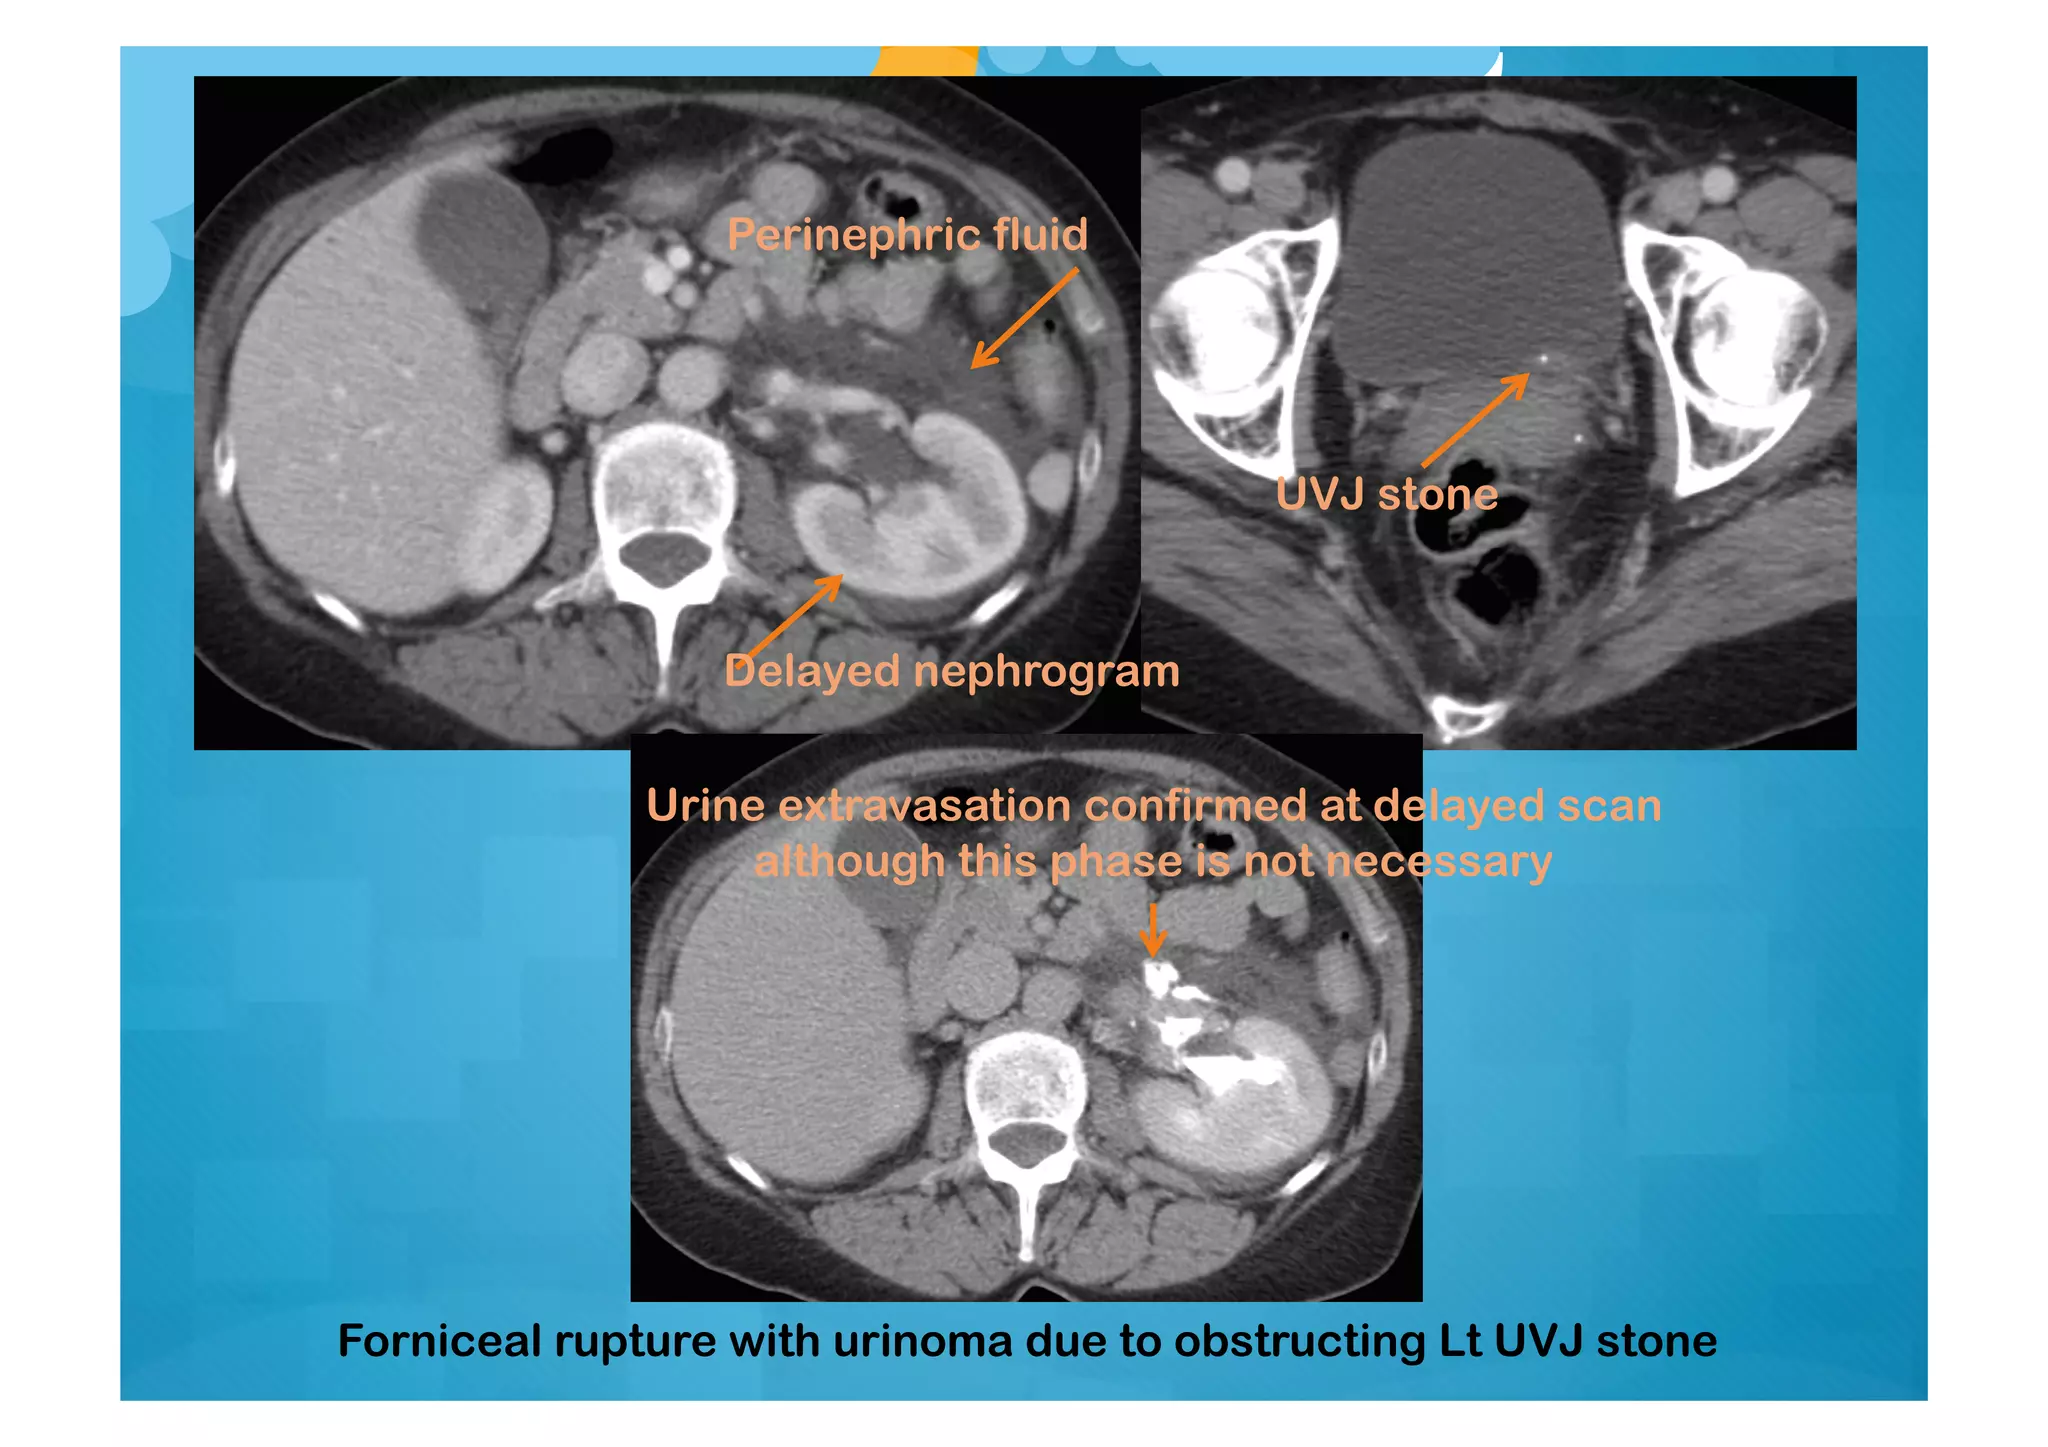

Forniceal rupture with urinoma due to obstructing Lt UVJ stone

UVJ stone

Delayed nephrogram

Perinephric fluid

Urine extravasation confirmed at delayed scan

although this phase is not necessary

Forniceal rupture withurinoma due to obstructing Lt UVJ stone UVJ stone Delayed nephrogram Perinephric fluid Urine extravasation confirmed at delayed scan although this phase is not necessary